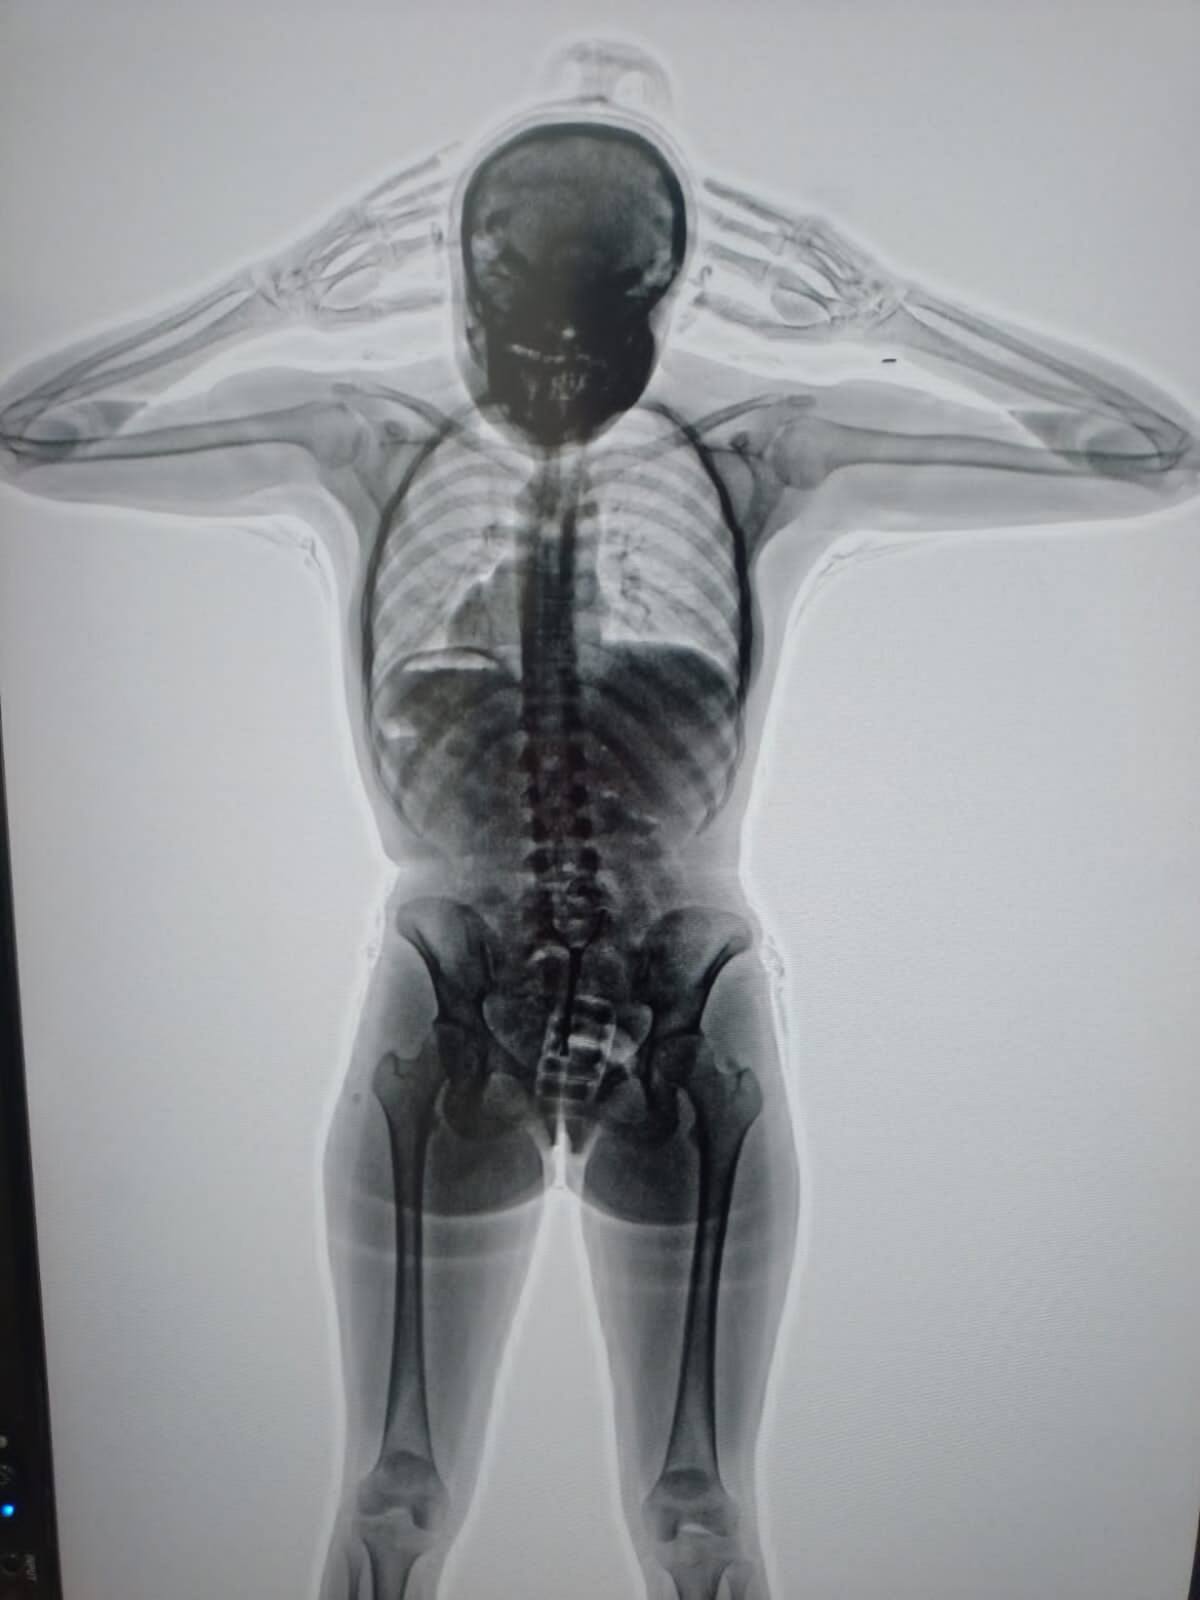

El body scan que detectó la presencia de cocaína en el cuerpo de la detenida. Foto: PSA.

Así, procedieron a una inspección de las pertenencias de la pasajera, que resultó negativa. Sin embargo, sus dudas persistían, por lo cual, con la colaboración de la Policía de Seguridad Aeroportuaria (PSA), procedieron a realizarle un body scan que arrojó imágenes comprometedoras.

En efecto, se advertía la presencia de cuerpos extraños en su organismo. Concretamente, había introducido en su vagina un profiláctico con 11 cápsulas de cocaína, de aproximadamente 10 gramos cada una.